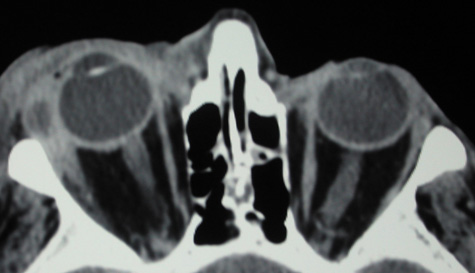

An extraconal or intraconal mass may be present in orbital cellulitis. Proptosis also may be visible. In particular, with intraconal involvement, proptosis is seen with obliteration of the normal soft tissue shadows. “Patchy enhancement” of the intraconal fat in orbital cellulitis has been described.59 The rectus muscles, particularly the medial rectus, and the optic nerve may be thickened.58

CT is particularly useful for imaging orbital and subperiosteal abscesses. Because the periorbit is not adherent to the orbital walls except at the suture lines, an abscess lifts the periorbit, creating a convexity in the orbital periosteum (Fig. 16). Usually subperiosteal abscess formation occurs adjacent to the involved sinus,25,64 but occasionally it occurs at a remote location such as the superolateral orbit.65 Gas may be found within a subperiosteal abscess or within the orbit, arising either from gas-forming bacilli or free communication with sinus air or from prior trauma (Fig. 17). 57,66 CT cannot accurately predict whether a subperiosteal mass represents exudate, inflammatory transudate, or hematoma.67,68

Fig. 16. Computed tomography showing subperiosteal abscess formation. Note elevation of orbital periosteum and convexity as pus elevates periorbit from the medial orbital wall.

A subperiosteal abscess may rupture or invade the periorbit, resulting in an orbital abscess. This may or may not be contiguous with the subperiosteal collection on CT. There may be gas or air–fluid levels within the mass.51,56,58,59 An orbital abscess may present as an enhancing ringlike peripheral mass that can be either heterogeneous or homogeneous (Fig. 18).

Fig. 18. Orbital abscess. A. Computed tomography of an orbital abscess presenting as an enhancing intraconal mass on right side. B. T1-weighted image. C. T2-weighted image. Note area of high signal corresponding to abscess.